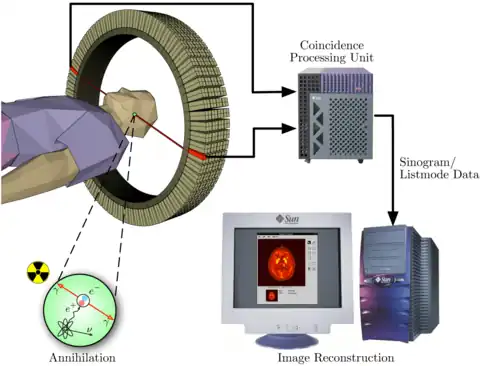

La TEP repose sur le principe général de la scintigraphie qui consiste à injecter un traceur dont on connaît le comportement et les propriétés biologiques pour obtenir une image du fonctionnement d'un organe ou la présence d'une cible moléculaire. Ce traceur est marqué par un atome radioactif (carbone, fluor, azote, oxygène, etc.) qui émet des positons dont l'annihilation produit deux photons. C'est la détection en coïncidence de ces photons qui permet la localisation de leur site d’émission et donc la concentration du traceur en chaque point de l'organe. C'est cette information quantitative que l'on représente sous la forme d'une image faisant apparaître en couleurs les zones de forte concentration du traceur.

Une caméra TEP est un appareil qui a l’aspect d’un scanner mais son principe de fonctionnement est différent. En effet, l'atome radioactif (par exemple, le fluor 18) se désintègre en émettant un positon. Celui-ci va s'annihiler avec un électron du milieu, après un très court parcours de l'ordre du millimètre (0,6 mm dans l'eau pour le positon du 18F). Cette annihilation produit deux photons gamma de 511 keV qui partent sur une même direction mais dans un sens opposé, ce qui rend possible le traitement tomographique des données. En effet, les capteurs situés tout autour du patient détectent les photons d'annihilation en coïncidence (c’est-à-dire ceux qui arrivent en même temps), ce qui permet d'identifier la ligne sur laquelle se situe l'émission des photons. Un système informatique reconstitue ensuite à l'aide d'un algorithme de reconstruction les images de la répartition du traceur au niveau d’une partie ou de la totalité du corps sous la forme d'une image 2D ou d'un objet 3D. Les images ainsi obtenues sont dites « d’émission » (la radioactivité provient du traceur injecté au patient). La résolution spatiale de l'image ainsi obtenue est comprise entre 4 et 7 mm en imagerie clinique (pour l'homme) et inférieure à 1,5 mm en imagerie préclinique (destinée au rat ou à la souris)[7].